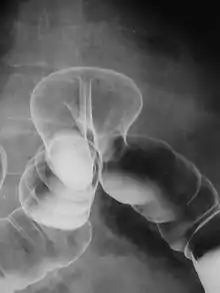

حُقَن الباريوم سِلسِلَة الجهاز المعدي المَعَوِيّ الّسُفلِيّ، وأَيضاً تُسَمّى (حُقنَة البَاريوم):هو إجراء طِبّي يُستَخدَم لإيجاد المُشكِلات المُتَعَلِّقة بالقولون (الأمعاء الغليظة)،يَتِم أخذ صورة بالأشعَّة الّسينيّة بَينَما تُملأ مادّة كبريتات الباريوم بالقولون، التي يَتِم إدخالها من خلال المستقيم (الجزء الأخير من الأمعاء الغليظة).[1][2]

يُمكِن إجراء هذا الفَحص في المستشفى أو في العيادة الّصحيّة، يَأخُذ المريض الوضعيَّة المُناسِبة على الّطاولة لِيَتِم أخذ صورة أشعّة إكس (الأشِعّة الّسينيَّة) الّتمهيديّة، يُطلَب من المريض بعدها أن يَستَلقي على جانبِه ليَتِم إدخال أنبوب حُقنة شَرجيّة مُزَيَّت بِشَكِل جَيِّد عبرَ المُستَقيم، في الوقتِ الذي يَتِم فيه إدخال أُنبوب الحُقنَة إلى داخلِ الجِسم، من المُمكِن أن يَشعُر المريض بشعورٍ يُشبِه حَركِة الأمعاء(تَغَوُّط). كبريتات الباريوم :هي مادّة ظليلة للأشعّة(تَظهَر باللون الأبيض في صورة أشعة اكس)،يُسمَح لها بالّتدَّفُّق وصولاً إلى القولون، يَتواجَد على رأسِ أنبوب الحُقَن بالون كبير، حيثُ أنَّه من المُمكِن نَفخُه للحِفاظ على كبريتات الباريوم في الّداخل،يقوم مُقَدِّم الّرعاية الّصحيّة بمُراقَبِة دخول و تَدَّفُّق مادِّة كبريتات الباريوم باستِخدام ستار الأشعّة الّسينيّة والّتنظير التألُّقي (مثل شاشة الّتلفاز)،يُنفَخ الهواء داخل القولون لتَمديده وبالّتالي الحصول على صورةٍأفضل(عادةً ما يُسمّى باختبار "مزدوج الّتبايُن").في حالة استخدام الهواء،يتم إعادة إدخال أنبوب الحقن إذا تمّت إزالتُه،ويتم تزويد القولون بكميّة صغيرة من الهواء، وتُؤخذ صور أشعَّة اكس إضافيّة. يُطلَب عادةً من المريض أن يأخُذ وضعيَّات مُختَلِفة، وتُمَيَّل الّطاولة بشكل خفيف للحصول على عدد من المُشاهَدات المختلفة . إذا تَواجَدَت شُكوك حَول احتماليّة وجود ثُقب في الأمعاء، يَستخِدم مادّة تباينيّة أخرى تَذوب بالماء كعامل بديل عن الباريوم، وتكون الإجراءات الأخرى متشابِهة، بالّرغم من أنَّ الّصورة ستكون أقل جَودة، في حالةِ وجود الانثقاب، ستتسرَّب المادّة من المِعَى(جمع أمعاء) إلى الّتجويف البيرتوني(جوف الّصفاق)، المادّة القابِلة للذَوَبان بالماء أقلّ تعتيماً بالمُقارنَةِ من الباريوم، ستظهر الحاجة لعمل شق بطني من أجل إزالة المادّة الّتبايُنيّة.

حُقَن الباريوم هي أكثر الّطرق المُستَخدَمة شيوعاً للتحقُّق من صِحة الأمعاء؛ فَهي تُساعِد في تشخيص و تقدير طبيعة و مدى أمراض الأمعاء الالتهابيّة مِثِل: التهاب القولون الّتقرُّحي، وداء كرون، يُمكِن مُشاهَدِة الّزوائِد اللحميّة، وعلى الرُّغم من ذلك لا يتم إزالتها خِلال الفحص كما هو الحال في تنظيرِ القولون-من الممكن أن تكون سرطانِيّة، هُناك مشاكل أُخرى كالُّرُتاج أو داء الّرُتوج(أكياس صغيرة تتشكّل على جِدار القولون ومِن المُمكن أن تلتهب)،و الانغلاف يُمكن أن تَظهر في هذا الاختبار (في بعض حالات الانغلاف يُمكن للاختبار نفسه أن يُعالجها).أيضا يُمكِن مُلاحظة وجود التهاب الّزائدة الّدودية الحادّ أو التواء عروة من الأمعاء، إذا كانت الّصورة طبيعيّة فيُمكِن اعتبار وجود مُسبِّب طبيعي وظيفي مثل: مُتلازِمة القولون المُتهيِّج. يجب أن يَملأ الباريوم القولون الّسليم بِشَكِل موَحَّد و مُنتَظِم بِحَيث يظهر كل من كِفاف (مُحيط) الأمعاء بِشَكِل طبيعي، الّسالِكيًة(ينبغي أن تكون مفتوحة بحريًة) والوَضعيّة.